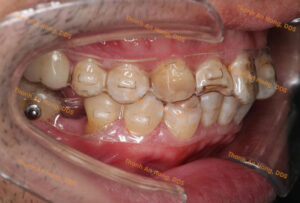

HÌNH ẢNH THỰC TẾ

Chỉnh mắc cài giảm hô